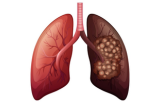

Kanker is een ziekte die gekenmerkt wordt door de ongecontroleerde proliferatie van cellen als gevolg van genetische mutaties die de normale celcyclus verstoren. In tegenstelling tot normale cellen verliezen kankercellen hun vermogen om te reageren op signalen die de celgroei en -deling reguleren en krijgen ze de capaciteit om zich oneindig te delen. Deze gemodificeerde cellen vermenigvuldigen zich ongecontroleerd en vormen tumoren die omliggend weefsel kunnen binnendringen en vernietigen. Bovendien kunnen kankercellen zich losmaken van de oorspronkelijke tumor en zich verspreiden naar andere delen van het lichaam, een proces dat metastase wordt genoemd. Onderscheidende kenmerken van kankercellen zijn onder andere hun vermogen om aan geprogrammeerde celdood te ontsnappen en de vorming van nieuwe bloedvaten op gang te brengen om hun toevoer van zuurstof en voedingsstoffen veilig te stellen. Deze kenmerken maken kanker tot een complexe en multifactoriële ziekte die een grondig begrip van de mechanismen vereist om effectieve behandelingsstrategieën te kunnen ontwikkelen. Kortom, kanker is het resultaat van de progressieve transformatie van normale cellen in kankercellen, die hun controle over groei en deling verliezen en het vermogen krijgen om uit te zaaien, waardoor de gezondheid van het organisme wordt bedreigd.